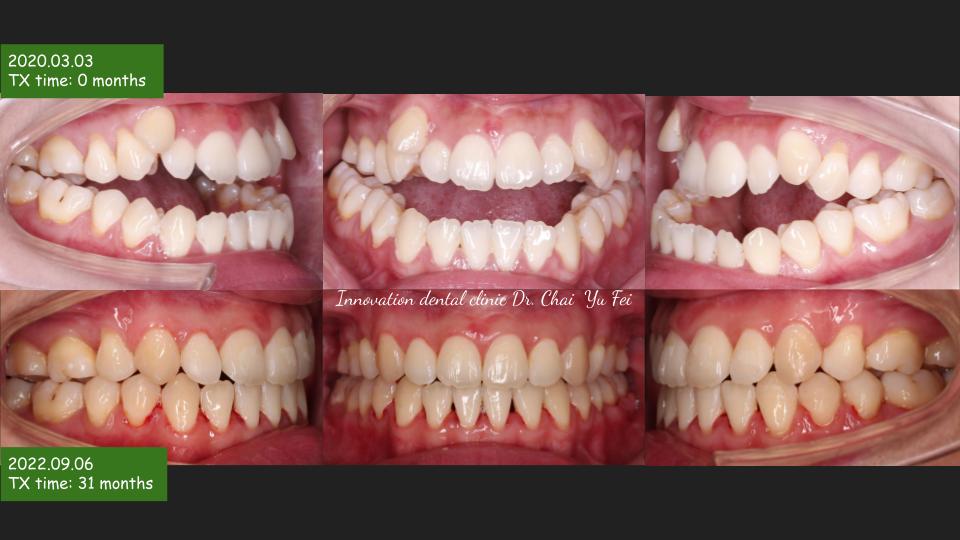

以這次分享的W同學案例來說,W同學原本就有很好的外型,只是因為骨性戽斗,造成咬合不正,前牙呈現開咬,這樣的狀態已經困擾她超過十年以上。因緣際會透過寰宇牙醫診所-林裕崧醫師介紹來展心展研做諮詢,經過我的臨床診斷後,斷定這是需要合併「正顎手術」的矯正案例,也因此我決定與「矯正跟口腔外科雙專科」的蔡佩晏學姊合作。

謝謝W同學忍受術後那些不方便的時刻,最終能有這樣的結果大家都很開心,很想跟大家說:OGS(正顎手術合併的矯正治療)其實不可怕,只要經過仔細評估與規劃,就可以很完美的調整臉型與咬合!

シャクレ、長い顔、アシンメトリなどはいずれもOGS(顎矯正手術:Le Fort1+BSSO;上下顎骨切り)によって治療が予定です。